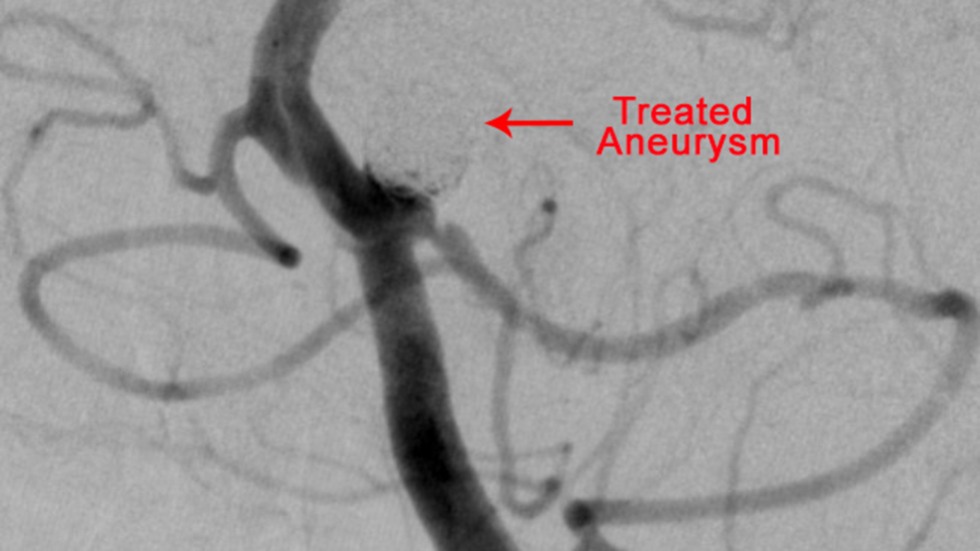

Balloon-Assisted Coiling

Balloon Assisted Coiling: Balloon-assisted coiling is used to treat wide-necked (opening too large to keep the coil in place), complex-shaped cerebral aneurysms.

Balloon-Assisted Coiling: Treated Aneurysm

3 of 3